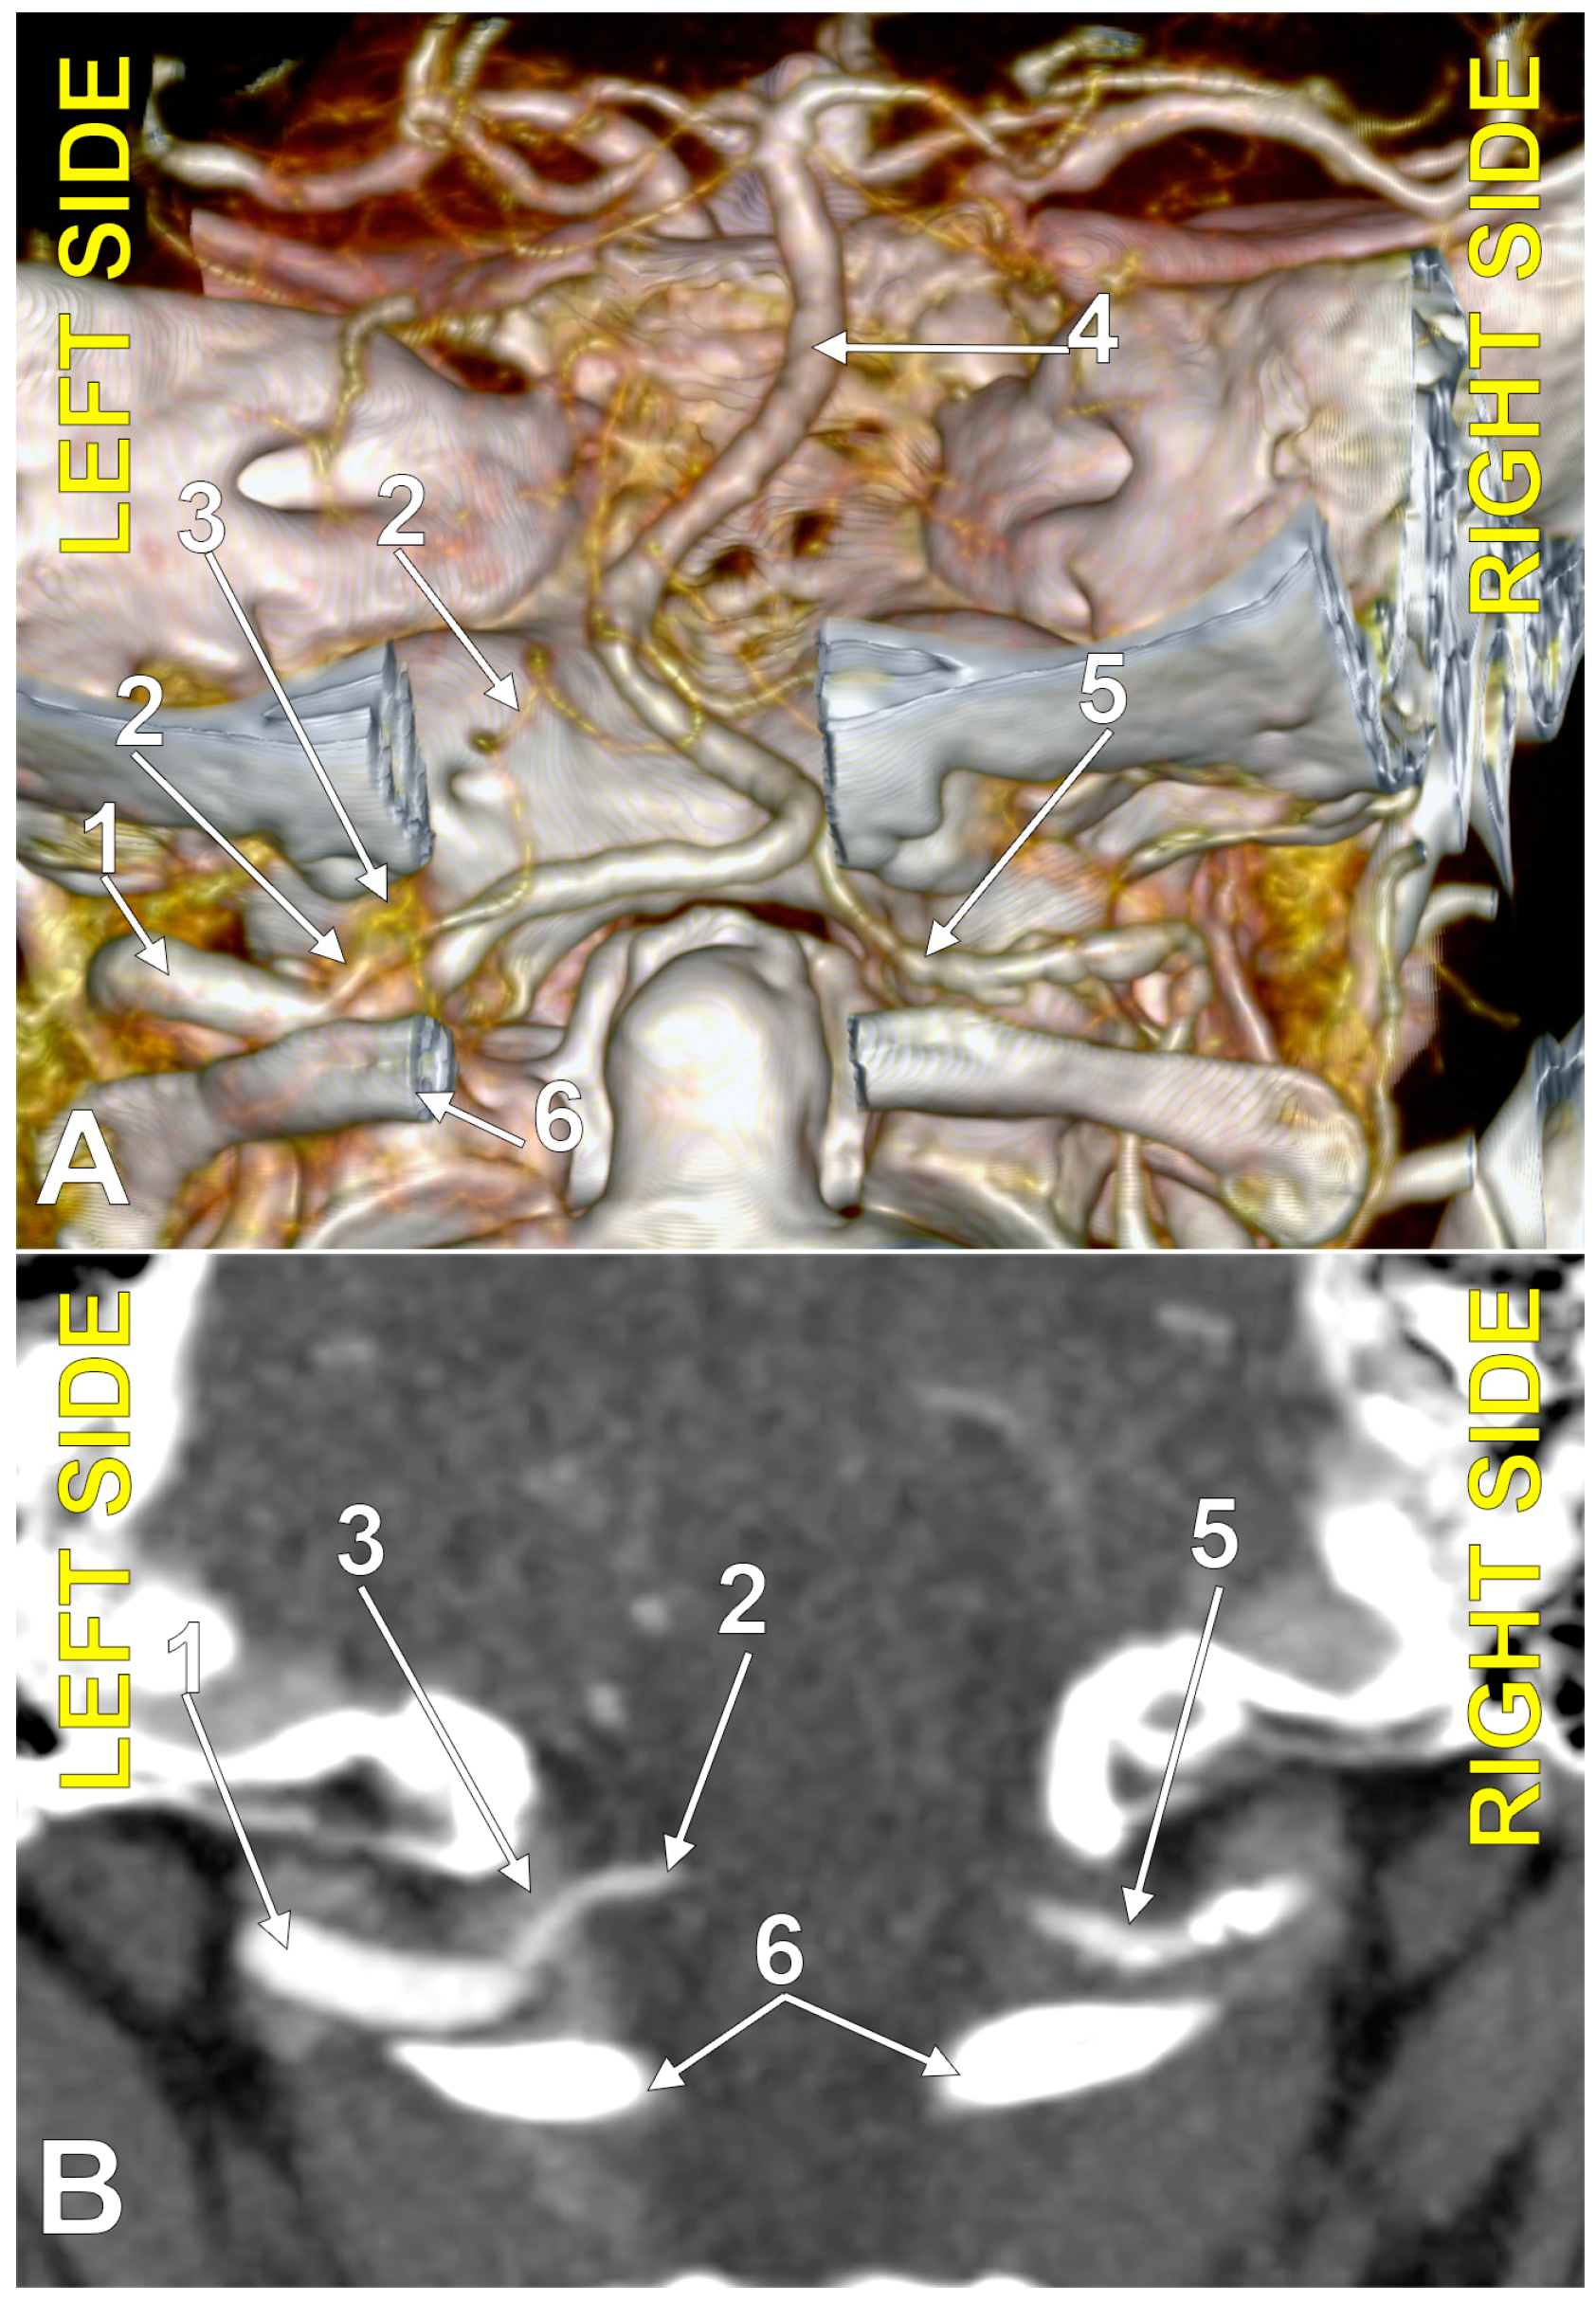

4.5. The PICA and the Marginal Sinus

4.6. The PICA and the Dural Ring of the VA